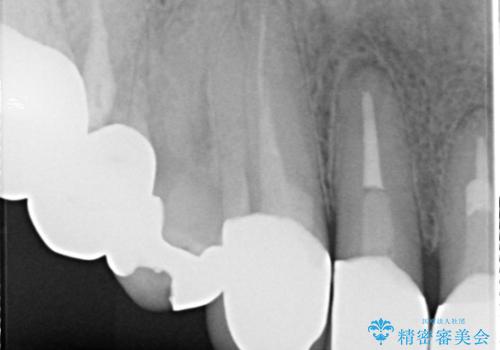

適合不良のかぶせ物が装着されていた歯は、内部がやはり虫歯になっていました。

かぶせ物だけではなく見えないところも、精密な治療をすることが重要となります。